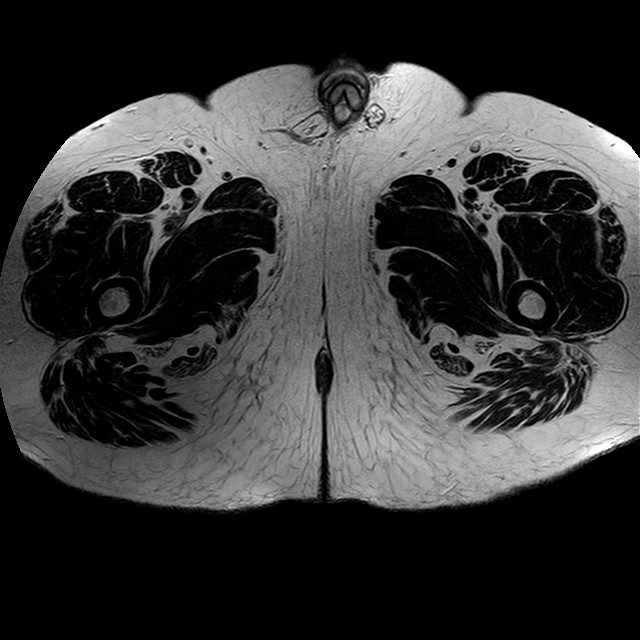

Esami: RMN BACINO

eT2w TSE

Evidenti e simmetriche alterazioni osteofitosiche in regione coxo femorale con riduzione delle rime articolari. Degenerazione completa del cercine glenoideo. Non attuali segni di versamento articolare. Non segni di edema osseo che escludono attuale algodistrofia od osteonecrosi. Lieve e simmetrica riduzione del trofismo della muscolatura glutea.